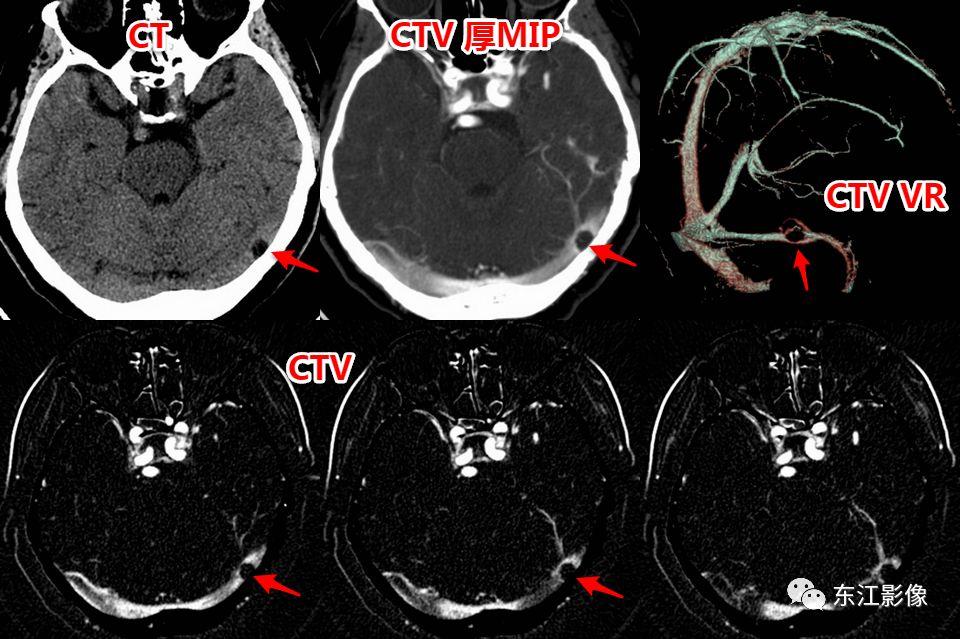

2. 静脉窦内扩大的蛛网膜颗粒

- 蛛网膜在硬脑膜构成的静脉窦附近形成许多绒毛状突起,突入静脉窦内,形成静脉窦内蛛网膜颗粒。

- 随着头颅MRI的广泛使用,静脉窦内扩大的蛛网膜颗粒“变得”非常常见。

- 不熟悉的话,容易误诊为异常。

- 以横窦常见(横断面图像最容易被发现的缘故),其次为上矢状窦,直窦、乙状窦少见,海绵窦罕见。

- CT平扫,呈稍高密度背景内低密度充盈缺损。

- MRI T1WI为低信号,稍高于脑脊液信号;T2WI为高信号,FLAIR多为低信号,稍高于脑脊液信号,较大的其内可见絮状稍高信号;增强多无强化,较大的其内可见点、线状强化灶。MRV上均呈附壁状充盈缺损。

- 极少数静脉窦内扩大的蛛网膜颗粒可能会引起静脉窦狭窄,DSA实时压力测量是确诊工具。

右侧横窦扩大的蛛网膜颗粒。

左侧横窦扩大的蛛网膜颗粒。

上矢状窦、直窦多发扩大的蛛网膜颗粒,薄层T2WI切线面显示更佳。